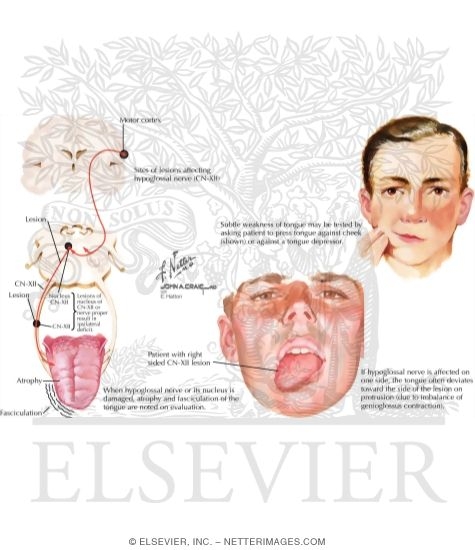

Hypoglossal Nerve (CN-XII)

Hypoglossal Nerve (CN-XII)

Hypoglossal Nerve (CN-XII)

Hypoglossal Nerve (CN-XII)